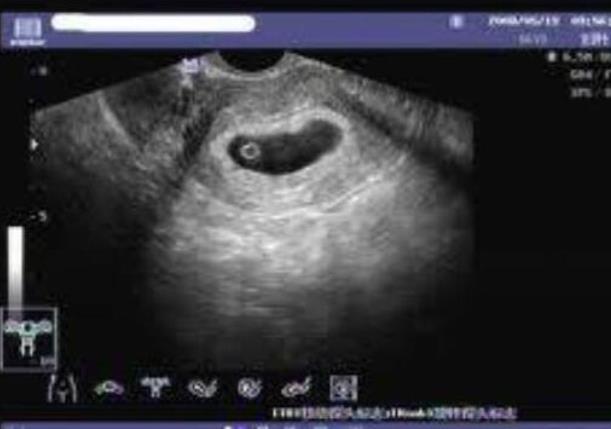

安徽供卵試管 2023在安徽省立醫(yī)院做供精試管需要滿足什么條件? ‘孕囊形狀看男女在孕多少天比較準(zhǔn)’